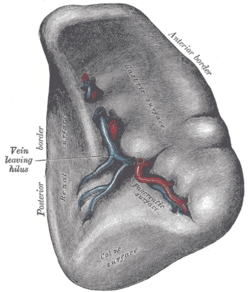

Surfaces

The diaphragmatic surface of the spleen (or phrenic surface) is convex, smooth, and is directed upward, backward, and to the left, except at its upper end, where it is directed slightly to the middle. The spleen lies beneath the left diaphragm, beneath the ninth, tenth, and eleventh ribs. The diaphragm separates the spleen from the pleura and base of the left lung.

The visceral surface of the spleen is divided by a ridge into two regions: an anterior or gastric and a posterior or renal. The gastric surface is directed forward, upward, and toward the middle, is broad and concave, and is in contact with the posterior wall of the stomach. Below this it is in contact with the tail of the pancreas.

The renal (kidney) surface is directed medialward and downward. It is somewhat flattened, considerably narrower than the gastric surface, and is in relation with the upper part of the anterior surface of the left kidney and occasionally with the left adrenal gland.

Blood supply

Near the middle of the spleen lies a long fissure, the splenic hilum. The hilum is the point of attachment for the gastrosplenic ligament, and the point of insertion for the splenic artery and splenic vein. There are other openings present for lymphatic vessels and nerves.

Like the thymus, the spleen possesses only efferent lymphatic vessels. The spleen is part of the lymphatic system. Both the short gastric arteries and the splenic artery supply it with blood.[11]